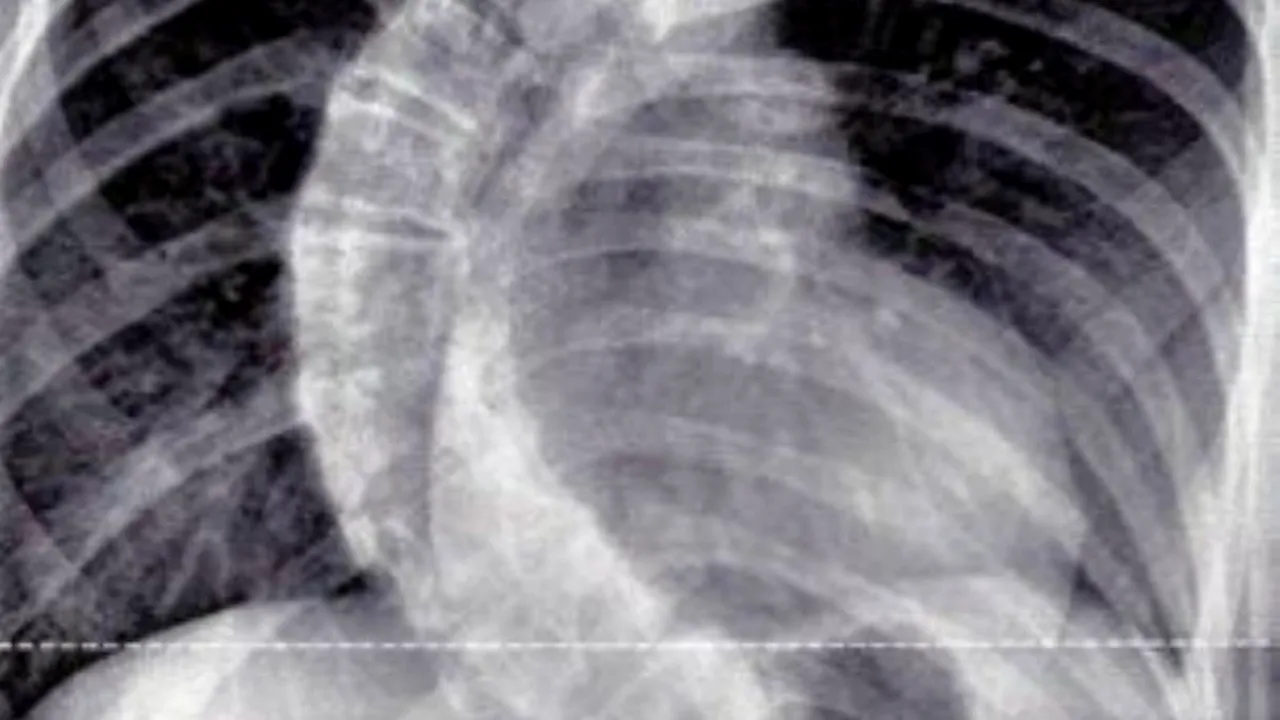

Coloana vertebrală a lui Emily Crosby, o britanică în vârstă de 13 ani, era curbată la 90 de grade și răsucită la 50 de grade. Medicii au fost șocați atunci când au analizat radiografiile copilei. Imaginile i-au făcut să exclame că acesta este cel mai grav caz cu care s-au confruntat.

Ajunsă la spital, medicii au decis să îi facă o radiografie. „Când dat rezultatele, inițial am crezut că ni se arată imagini cu cel mai grav caz de scolioză. Dar în realitate, era o radiografie cu coloana vertebrală a fiicei mele. Am plâns foarte mult”, a mai spus femeia, în vârstă de 45 de ani.

FOTO. Daily Mail // În imagina din strânga se poate vedea cum arăta coloana britanicei Emily Crosby înainte de operație, iar în imaginea din dreapta, după operație